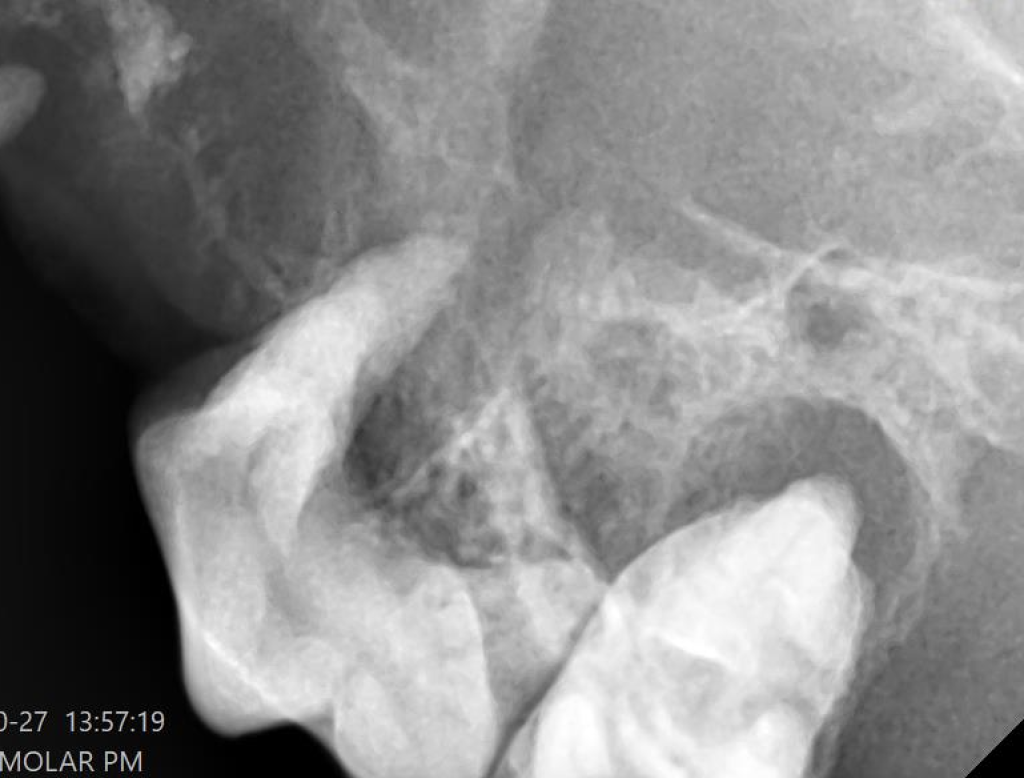

しかしながら、手術後の内科的治療が効を奏さず歯根部の歯周病は進行し、左上顎の第四前臼歯の歯周ポケットはかなり深くなっています。

レントゲンで確認すると、歯槽骨が融解して鼻腔に達していることがわかります。